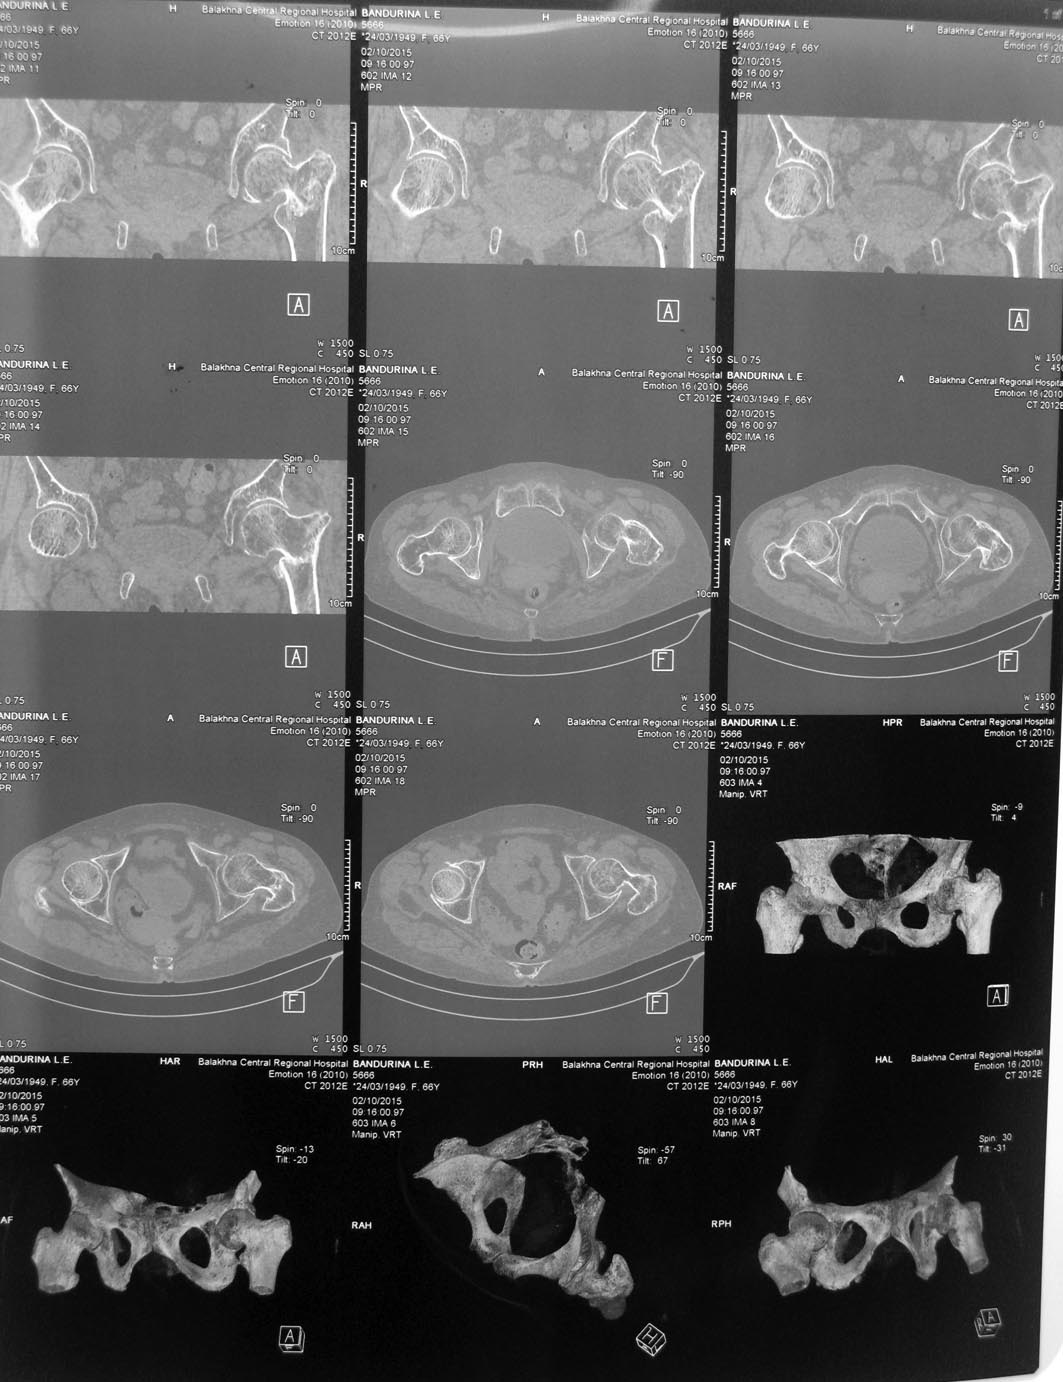

Добрый день! Обратилась женщина, 66 лет, лечится стационарно в неврологическом отделении по поводу болей в поясничном отделе позвоночника. В декабре получила чрезвертельный перелом левого бедра( упала), лечилась консервативно. В настоящее время ходит с умеренной хромотой, движения в левом тазобедренном суставе свободные, практически безболезненные. Укорочение конечности 2-3 см. Сама больная появление болей в позвоночнике связывает с укорочением конечности. При КТ позвоночника выявлена компрессия L2 на фоне остеопороза. Обратилась на консультацию с требованием коррекции длины конечности. Помогите, пожалуйста, с решением: 1.Целесообразно ли оперативное лечение в данном случае или достаточно коррекции ортопедической обувью 2.Если оперативное лечение,то корригирующая остеотомия или протезирование(учитывая возраст и наличие коксартроза на рентгенограммах)Заранее благодарен Кирилл

КТ

КТ избыточна, стандартной рентгенографии в двух проекциях вполне достаточно.